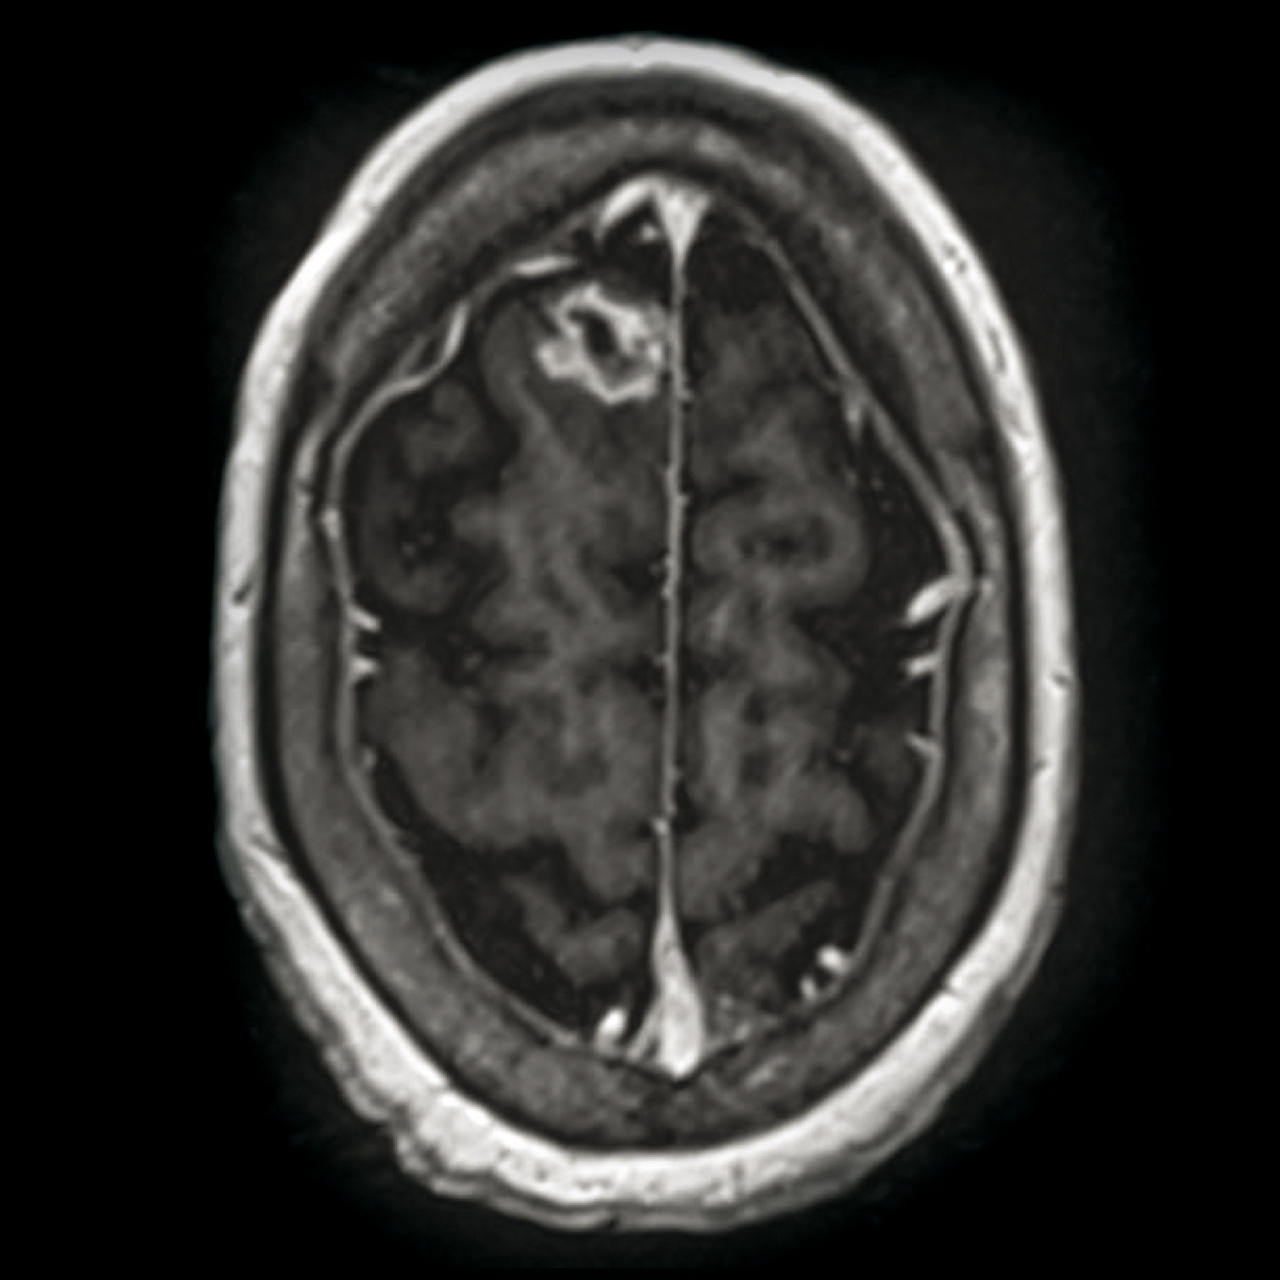

Quel est votre diagnostic ?

Il s'agit d'un aspergillome.